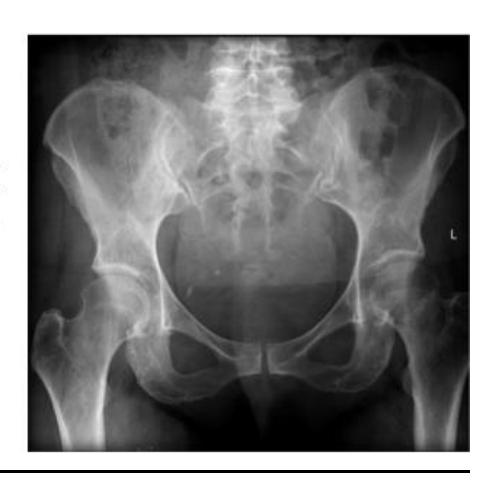

Give 2 abnormalities in this X-ray?

- Fracture of pubic bones

- Disrupted sacroiliac joint on the same side

Give first 2 measurements you need for saving life?

- ATLAS protocol (ABC)

- IV fluid administration

- IV analgesia

- Pelvic sheet application

A 13 years old patient, she is known to have idiopathic scoliosis. X-ray pelvis was requested for her.

- 1. Mention the name of the sign seen the X-ray.

- Risser sign

- 2. How it can help in taking decision the management?

- By assessing potential of growth to evaluate potential deformity progression (e.g. scoliosis)